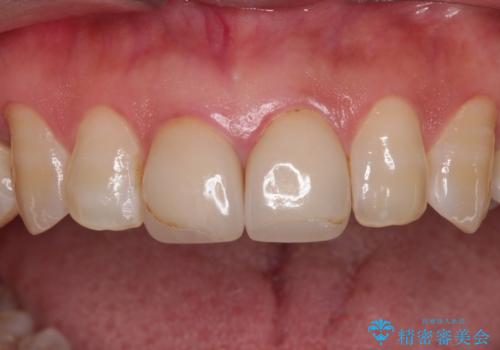

- つぎはぎのある前歯のセラミックの色合いが気になるとのことで来院された患者様です。

グレーの色が透けて見える気がする点が気になっていらっしゃり、やや黄色みのある色を希望されていました。